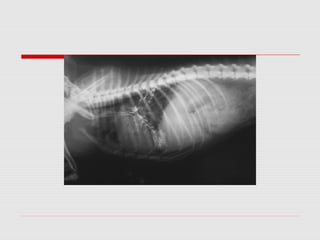

Mielograma toracolombar com compressão a nivel de L1-L2

Radiografía na posição latero-lateral : se observa um desvio do eixo das vértebras lombo-sacras

, proceso artrósico en L 6 - 7. Faltam apófisis espinhosas em L6-L7.